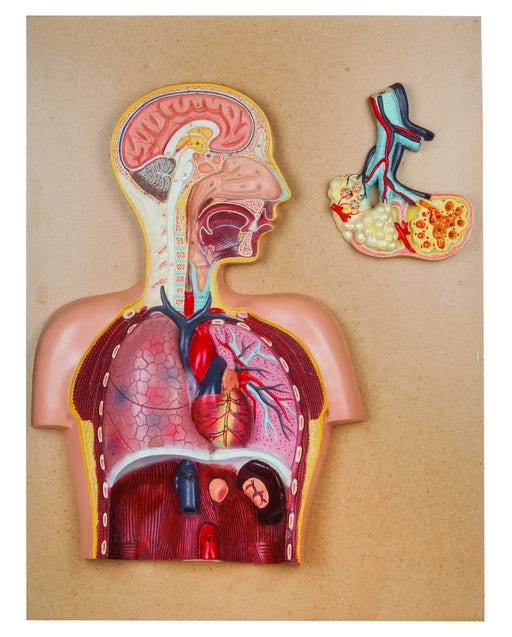

Model Respiratory System

Model shows L.S. of Head and brain, nasal cavity, heart, larynx with lungs and all important parts of our respiratory system. Showing L.S. of head...

View full detailsAM0284 -